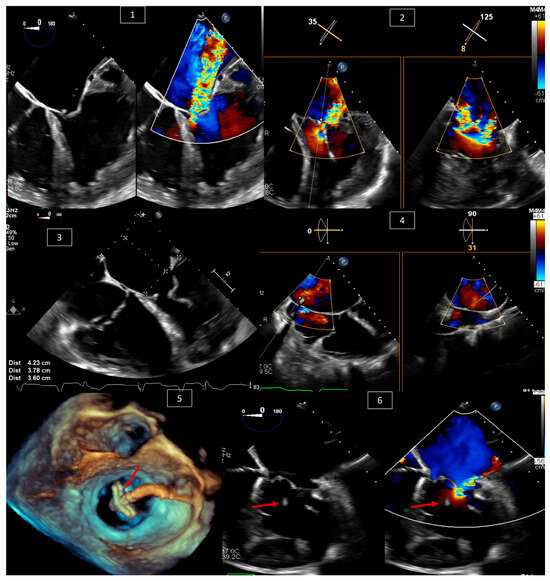

3. Ventricular Septal Defect (VSD) Closure